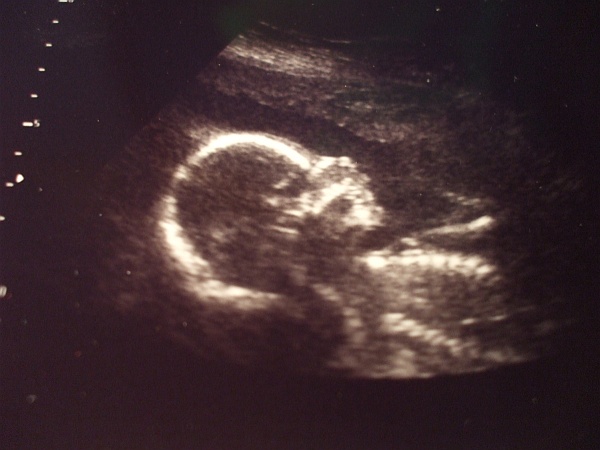

Nem is bálna

pocak csodaszép, meg te is

még kedvet kapok